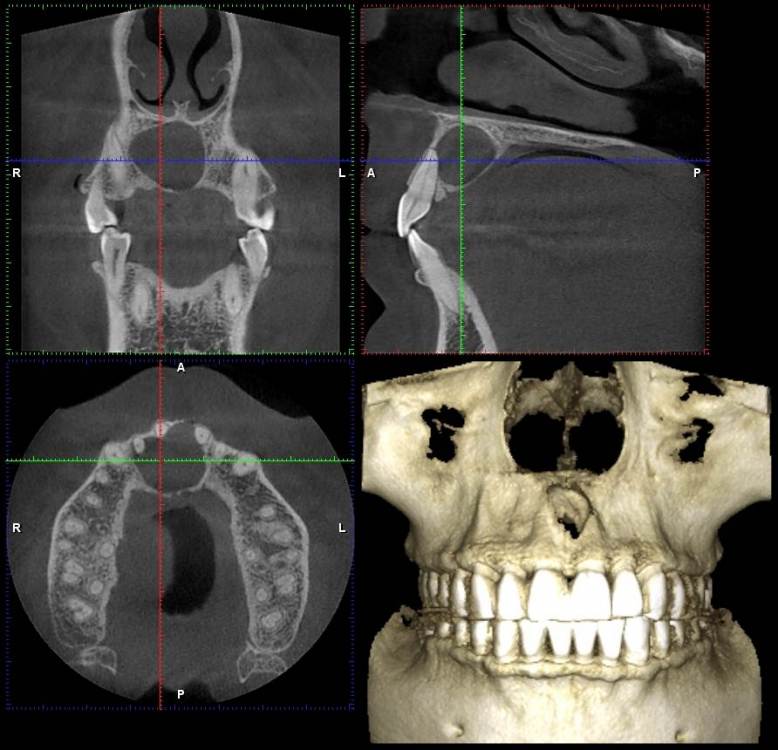

NazranDantist Опубликовано 3 декабря, 2021 Поделиться Опубликовано 3 декабря, 2021 Всем привет. Коллеги, вот такая ситуация обнаружилась на снимке. Со слов пациента, ничего не беспокоит, зубы интактные, травмы не было,холодовая проба положительная. Какую тактику лечения выбрать? Ну и в чем причина? Ссылка на комментарий

Irouil Опубликовано 3 декабря, 2021 Поделиться Опубликовано 3 декабря, 2021 Похоже на кисту резцового канала я бы пошёл на декомпрессию, потом удалил 4 3 Ссылка на комментарий

Irouil Опубликовано 4 декабря, 2021 Поделиться Опубликовано 4 декабря, 2021 39 минут назад, NazranDantist сказал: Спасибо. Как считаете, доступ небный делать? Или вестибулярной тоже зайти? Основной у Вас будет все равно небный, а если встретите сложности с диссекцией в области вестибулярной узуры (что навряд) - добавите второй. Ссылка на комментарий

kriokov Опубликовано 5 декабря, 2021 Поделиться Опубликовано 5 декабря, 2021 04.12.2021 в 11:27, Irouil сказал: добавите второй. не стоит, потеряет стенку вестибулярно, получит сквозной дефект. Если подпаяно в обл неба будет, всегда можно остро отойти Ссылка на комментарий